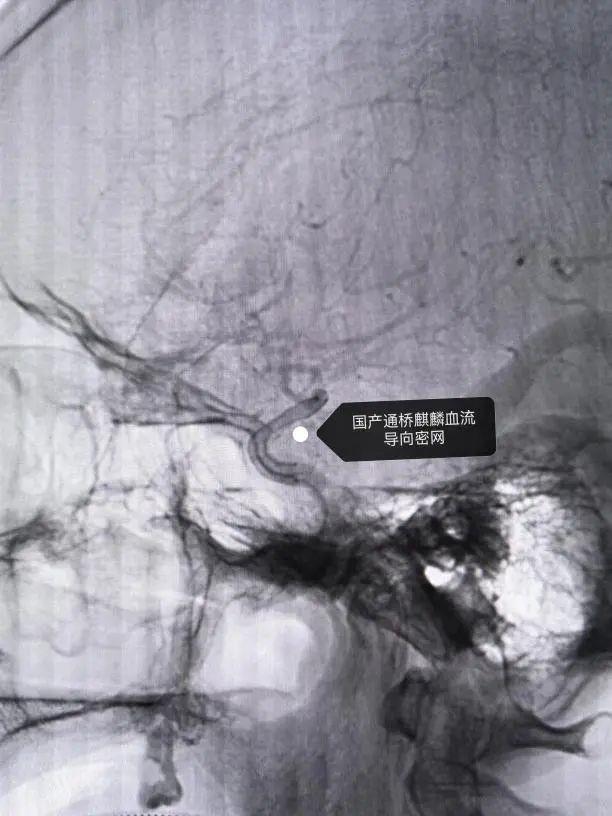

近日,六安市中医院神经外科一病区成功为一名复杂脑血管病患者实施 “支架辅助颅内动脉瘤栓塞术 +颈内动脉狭窄支架植入术”。

在神经外科杨建业主任与神经内科黄友发主任的紧密协作下,这例高风险手术仅用3小时完成,患者术后症状显著改善,已康复出院。该例

手术的成功实施,标志着医院在复杂脑血管疾病的一站式综合治疗上达到国内先进水平。

为确保手术安全,医院启动多学科会诊(MDT),联合神经内科、影像科等制定方案:打破常规顺序,先由神经介入团队对动脉瘤进行栓塞 “排雷”,再处理颈动脉狭窄 “通路”。“传统动脉瘤栓塞多用弹簧圈填充,而本例采用了更先进的密网支架技术。” 杨建业表示,这种类似 “细密滤网” 的支架植入动脉瘤开口后,可重塑血流方向,使瘤腔内血流停滞、逐渐闭塞,同时保留正常血管通路,对复杂形态动脉瘤的治疗效果更佳。

手术当日,杨建业首先通过股动脉穿刺,在血管造影引导下将微导管精准送达颅内,释放密网支架覆盖动脉瘤颈。造影显示,原本异常显影的动脉瘤腔内血流迅速减缓,“排雷” 成功。随后,黄友发接手,对左侧颈内动脉狭窄段进行球囊扩张并植入支架,狭窄程度从70%降至20%以下,远端脑血流恢复通畅。整个过程行云流水,术中患者生命体征平稳,未出现任何并发症。